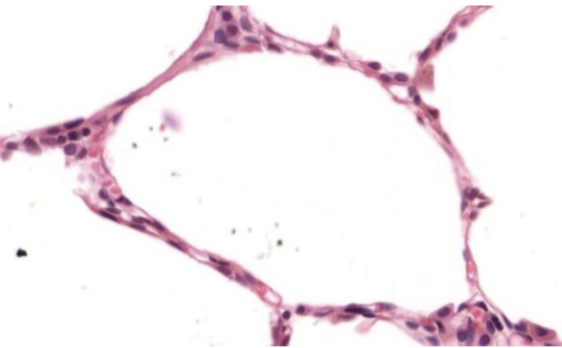

plano

Número de estratos

simple

Forma de sus células

plano

Número de estratos

simple

Indique órgano o sistema que posee este epitelio

alveolo